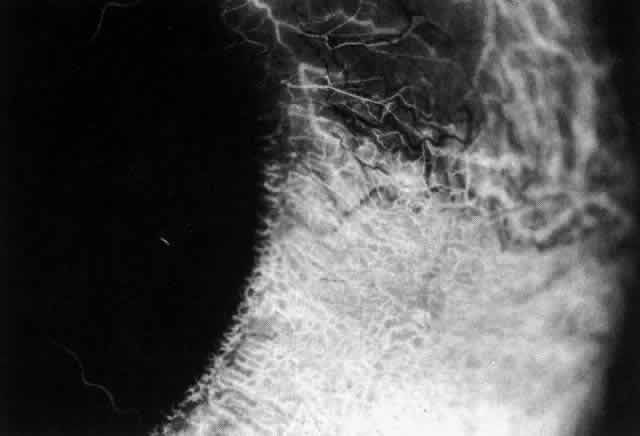

The characteristic features of necrotizing scleritis on fluorescein angiography

are hypoperfusion and, eventually, nonperfusion of the vascular

networks (Figs. 40 through 43).26 The initial changes are on the venous side of the capillary network; the

transit time of the dye increases even if the eye is red and congested. If

the disease process persists or has been present for a long time, thrombosis

and permanent vaso-occlusive changes occur. These vessels (or

the occluded capillary network) are bypassed by the opening of

anastomotic channels. New vessels in a granuloma give rise to deep intrascleral

leakage of dye (see Fig. 43). Conjunctival and episcleral involvement by the destructive change is

late but is always preceded by vaso-occlusive changes that can sometimes

Fig. 41. Late stage of fluorescein angiogram adjacent to the site of necrosis in

the same patient as in Figure 40. Although the eye is uniformly congested, the area near the necrosis shows

vascular shutdown, whereas the rest of the conjunctiva and episclera

is normally perfused. Fig. 41. Late stage of fluorescein angiogram adjacent to the site of necrosis in

the same patient as in Figure 40. Although the eye is uniformly congested, the area near the necrosis shows

vascular shutdown, whereas the rest of the conjunctiva and episclera

is normally perfused.

|

Fig. 42. Late arterial phase of fluorescein angiogram in a patient with necrotizing

scleritis. All the vessels except the main trunk and the vessels around

the limbal perforating vessels are occluded and remain unperfused

throughout the angiogram. Fig. 42. Late arterial phase of fluorescein angiogram in a patient with necrotizing

scleritis. All the vessels except the main trunk and the vessels around

the limbal perforating vessels are occluded and remain unperfused

throughout the angiogram.

|